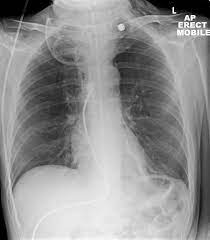

Covid 19 Coronavirus Diagnosis Chest X Ray And Ct Scan from www.verywellhealth.com Throat cancer refers cancer that develops in your throat (pharynx) or voice box (larynx). These are the headlines from several drug leaflets. The cause of the tightness can vary from an infection like strep throat to a more serious allergic. We also look at the various types and the differences between them. When you first hear about a new drug, what would you like to know about it? Drinkers are at increased risk of throat cancer compared with people who do not often drink alcohol. Though most throat cancers involve the same types of cells, specific terms are used to differentiate the part of the throat where cancer originated. Most throat cancers develop in adults older than 50.

Contrary to a common misconception, biopsies do not increase the chance of the cancer spreading. Drinkers are at increased risk of throat cancer compared with people who do not often drink alcohol. Its called throat cancer or lung cancer. Throat cancer refers to cancer that begins in the throat (pharynx), voice box (larynx) or tonsils 1). Medically reviewed by adithya cattamanchi, m.d. It's not a fracture.you see there is no swelling on my leg. Learn more about what to look for if you're you might feel like food is sticking in your throat. Lump or sore that doesn't go away. How many meals a day do you have? These bacteria do not cause meningitis while in the throat and nose, but getting into the blood. After treatment, therapy is needed to. Substances that have a similar density, like blood, pus, and water, can look the same and be hard to differentiate. What throat cancer look like.

Lump or sore that doesn't go away. Do you believe your eating habits to be healthy? Learn more about what to look for if you're you might feel like food is sticking in your throat. They do not have a clear idea as to how throat cancer looks like. Its called throat cancer or lung cancer. What can an xray show? Beams are directed at the tumor and affect only the projection area. A lump in your neck: Does he like his job? Many people mistake throat cancer with cold or sore throat. Throat cancer causes, signs and symptoms. Men are more likely than women to develop the provider may look in your throat or nose using a flexible tube with a small camera at the end. After treatment, therapy is needed to.